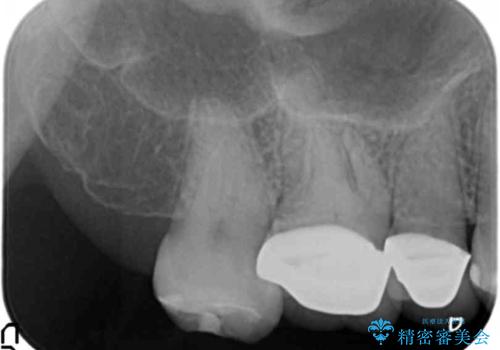

伸びてしまった奥歯、咬合平面を揃えたインプラント治療

インプラントを埋入するのに十分な骨は存在しますが、放置した間に上の歯が伸びてきてしまいクラウンのスペース不足な状態です。

通常このような場合、神経を除去し歯を短くしたのちインプラント治療を行いますが、今回はマイクロインプラントを用いて歯を歯ぐきの方向へ沈めたのち神経を温存する形でインプラント補綴を行いました。